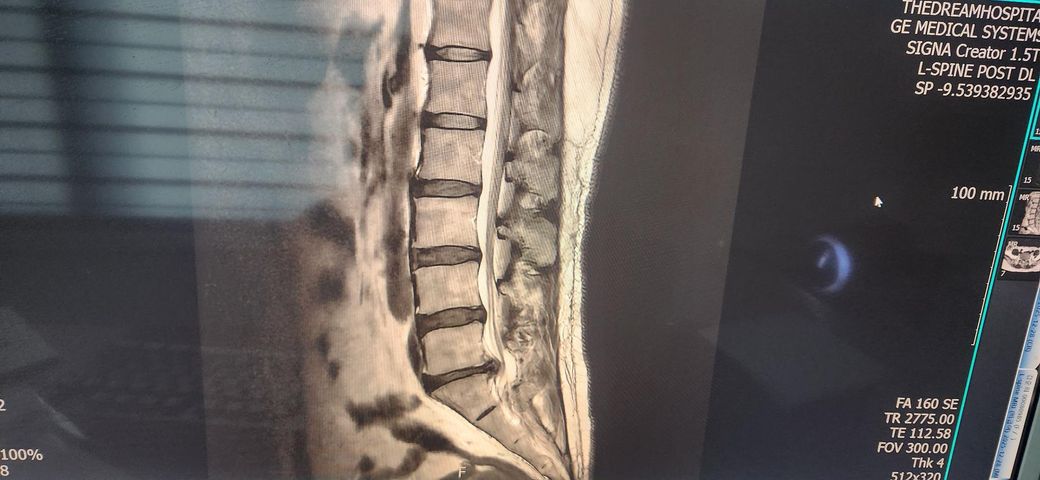

두번째부터는 수술 후 12월 30일 재촬영한 mri입니다.

수술 후 디스크가 잘 제거되지 않은것처럼 보이는데 1~2분씩만 만나주는 무성의한 의사는 지켜보잔 말뿐이네요.

수술 전에는 디스크가 크게 튀어나와 신경을 강하게 눌렀고, 수술 후 MRI를 보면 큰 디스크는 잘 제거된 상태입니다. 재발해서 다시 신경을 심하게 누르는 모습은 뚜렷하지 않습니다. 지금 있는 발가락 감각 이상, 종아리 저림, 약한 방사통, 엉덩이 뻐근함은

→ 눌렸던 신경이 회복되는 과정에서 흔히 나타나는 증상입니다.

응급수술을 할 만큼 압박이 심했던 경우, 이런 증상이 1-3개월, 길면 3-6개월까지 남는 게 흔합니다. 현재 상태는

회복이 느린편이지만 큰 문제상황은 아닌상태로 보는게 정확합니다. 의사가 지켜보자는 판단 자체는 맞는 대응입니다.